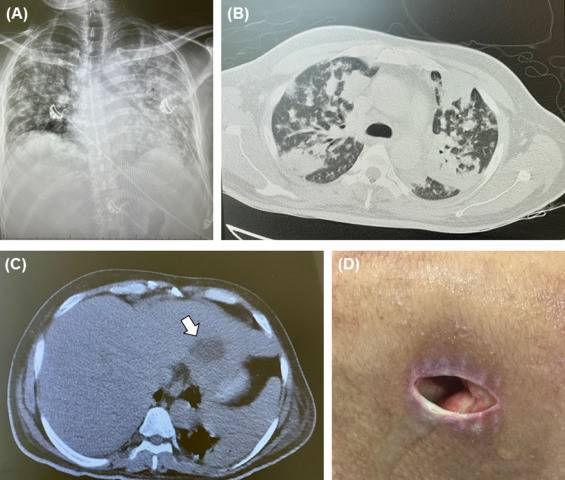

توصل فريق طبي في العاصمة الإماراتية أبوظبي الى لخطة علاجية جديدة للقضاء على مرض بكتيري نادر وخطر يسمى "متلازمة سيباسيا"، لتكون الامارات أول دولة بالعالم تبتكر خطة لعلاج هذا النوع من البكتيريا.

ونشرت المجلة الدولية للأمراض المعدية، التي تصدر تقاريرها من خلال الجمعية الدولية للأمراض المعدية، تقريرا عن تعافى مريض هندي يبلغ من العمر 42 عاما ويقيم بالإمارات، من "متلازمة سيباسيا" الخطرة.

وسلّط التقرير الذي أعده الفريق المعالج للمريض نيتش سادان مادجوكار بمدينة برجيل الطبية بأبوظبي، الضوء على المرض والأبحاث وخطة العلاج التي استخدمها فريق متعدد التخصصات.

وقالت إدارة مدينة برجيل الطبية في أبو ظبي، إنها استقبلت هنديا مصابا بالبكتيريا، وأخضعته لخطة العلاج الجديدة على يد فريق طبي من تخصصات مختلفة، حتى شفي تماما من المرض، معلنة أنه تم توثيق خطة العلاج بالمجلة الطبية لتكون مرجعًا يستفيد منه الأطباء بالعالم لعلاج الحالات المتشابهة مستقبلا.

وذكرت أن البكتيريا الخطرة التي كان يعاني منها المريض تتسبب في فشل العديد من أعضاء الجسم، ما يرفع نسب الوفاة.

وأوضح: "تمكنا من علاج المريض بنجاح باستخدام مزيج من المضادات الحيوية عن طريق الحقن الوريدي والاستنشاق، على مدار 54 يوما للتغلب على المرض".